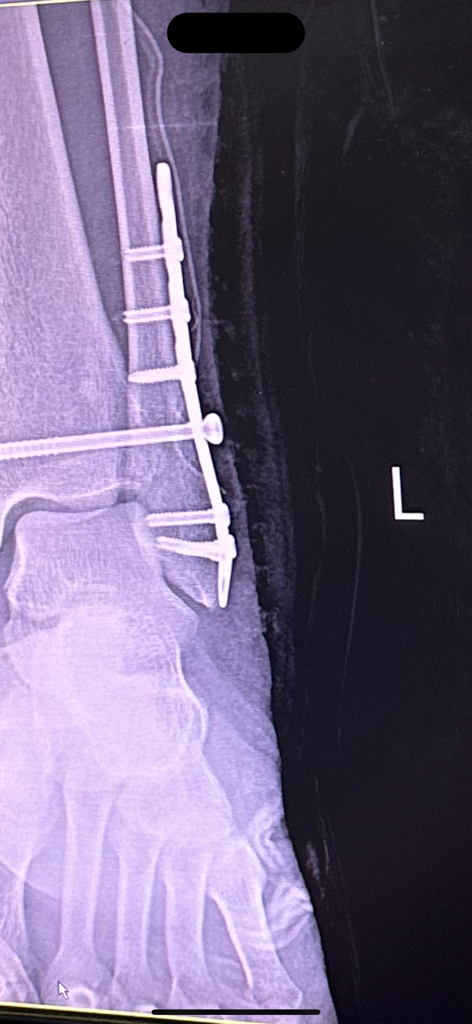

해당 엑스레이를 그당시에는 설명안하고 제가 내원했을 때 설명하시더라구요 "여기선 잘 안보여" 라고 하는데 일반인인 제가 여기있다고 말씀드렸습니다. 심지어 다른각도에서는 더 잘보이구요. 그래놓고 허겁지겁 다음 예약 잡자 말을 돌리시더라구요